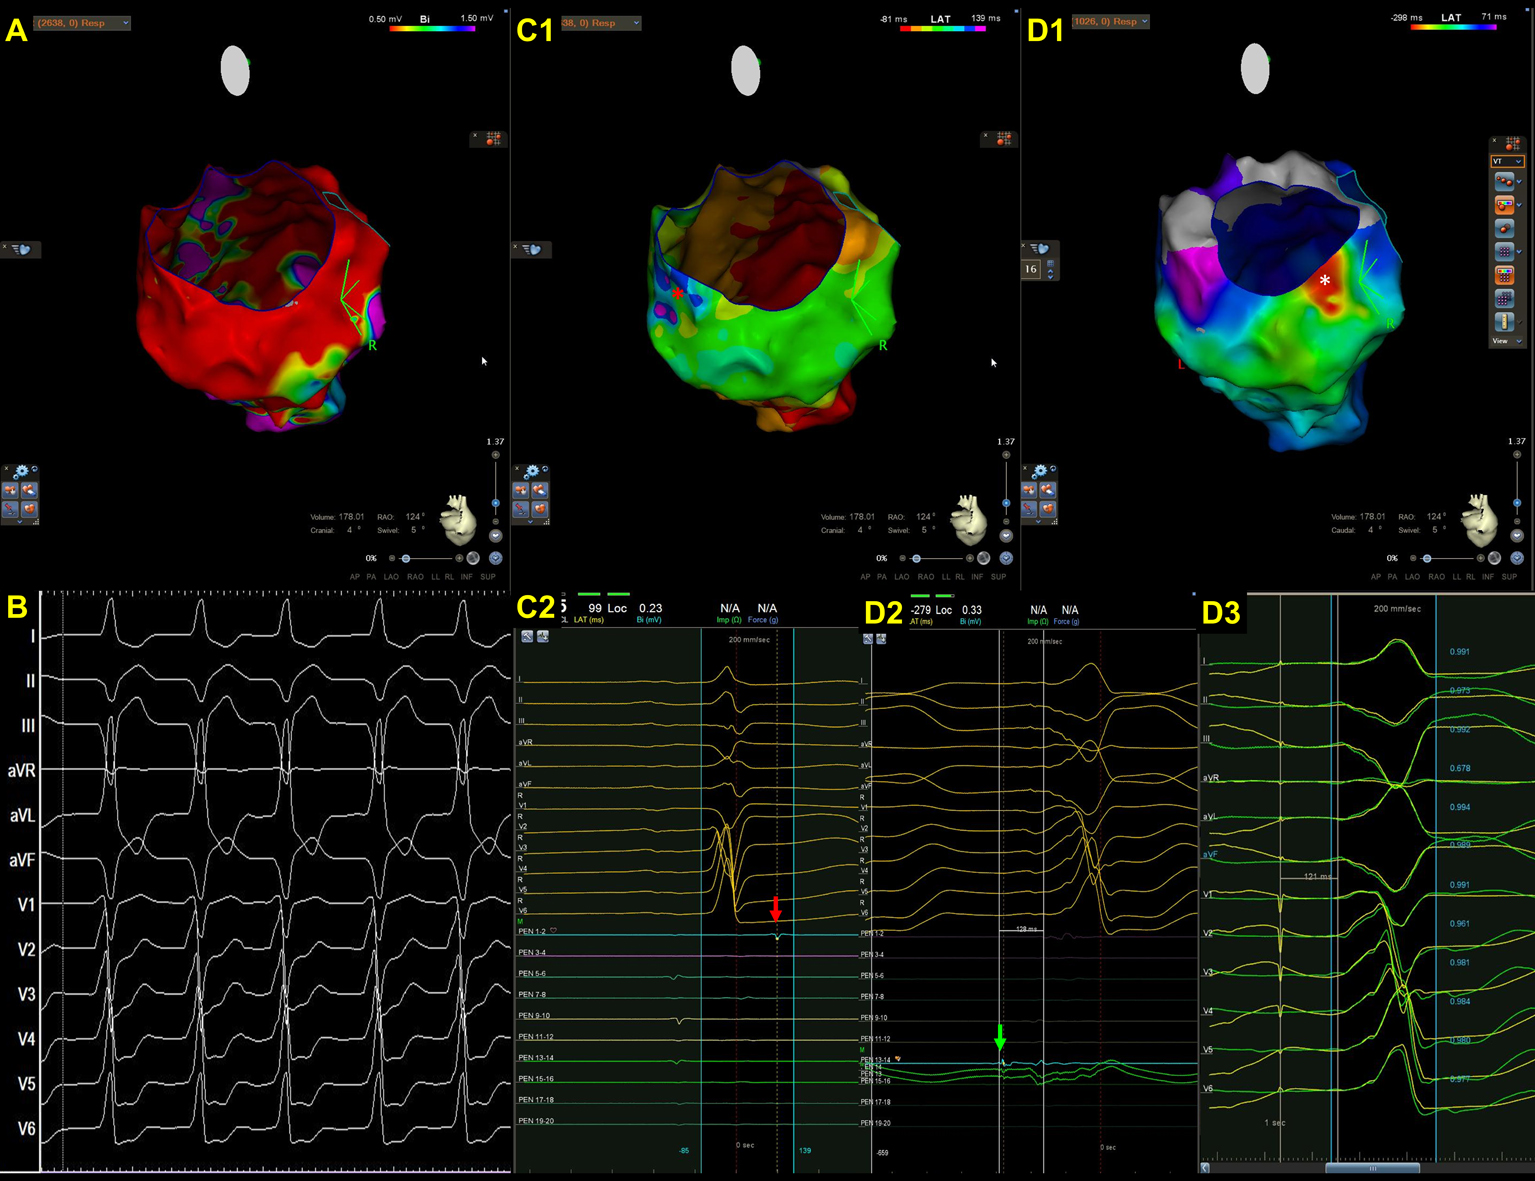

Fig. 1.A representative case of intramural ventricular tachycardia (VT) in a patient with arrhythmogenic left ventricular cardiomyopathy (ALVC) caused by titin mutation. Endocardial bipolar voltage (A) and preprocedural cardiac MRI (A2) revealed extensive scarring along the anterior septum and anterior wall, extending from the base of the LV to its apex. The scars identified by cardiac MRI are larger than those detected by endocardial bipolar voltage mapping owing to the presence of intramural scarring. (B1–2) An isochronal late activation map (B1) created by annotating the latest component of bipolar electrogram during right ventricular pacing and fractionated potential (B2) recorded within scar (red circle in B1). In particular, an isochronal crowding region was noted close to the scar border in the LV apex. (C1–2) VT activation map (C1), VT morphology and diastolic potential (C2). VT cycle length was 385 milliseconds with a left bundle branch block morphology and superior axis. The VT activation map (from red, orange, yellow, green, blue, indigo, to violet) demonstrated an incomplete circuit characterized by an activation gap (parts of the blue and violet are missing) within the endocardium. The mid-diastolic potential (red arrow, C2) was recorded at the blue dot site (C1). After radiofrequency energy was applied to the blue dot area, VT was terminated.

Ideally, the most important step is to induce clinically documented VT. We applied rapid ventricular pacing and programmed stimulation of up to three extra-stimuli from the RV apex and/or RVOT to induce VT in our laboratory [12, 81, 82]. When VTs are induced, QRS morphology and cycle lengths, either as documented by 12-lead ECG or intracardiac defibrillator (ICD), have been compared with those of clinically documented VTs [12, 81, 82]. Once the VTs are induced and mappable, activation mapping and entrainment mapping are employed to illustrate the VT circuits and identify critical isthmuses [83, 84]. It is noteworthy that since three-dimensional circuits are frequently observed in VTs and epicardial substrates are frequently observed in ACMs, an incomplete circuit characterized by an activation gap (Fig. 1) or endocardial/epicardial focal centrifugal activation pattern could be discovered [10]. Therefore, entrainment from the earliest activation sites and the adjacent scar is required to determine the potential exit or surrogate of reentrant circuits [85].